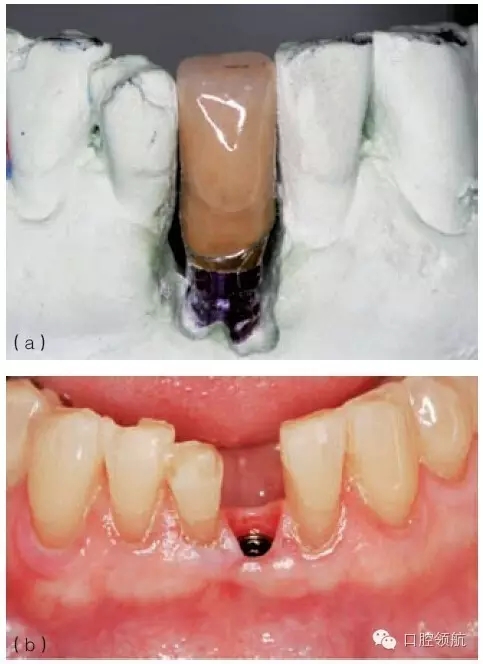

圖9.31 (a)對于深覆患者,當種植體植入角度偏頰側(cè)的時候,要相應增加植入深度,以避免下頜牙切緣與種植體接觸;增加操作空間,有利于形成逐漸過渡的修復體穿齦外形。(b)從種植體平臺到修復體頸部,逐漸過渡的臨時冠軸面外形。(c)臨時冠就位的臨床觀,在美學區(qū)域,對于非手術式的組織塑形,推薦2~3個月的塑形時間。